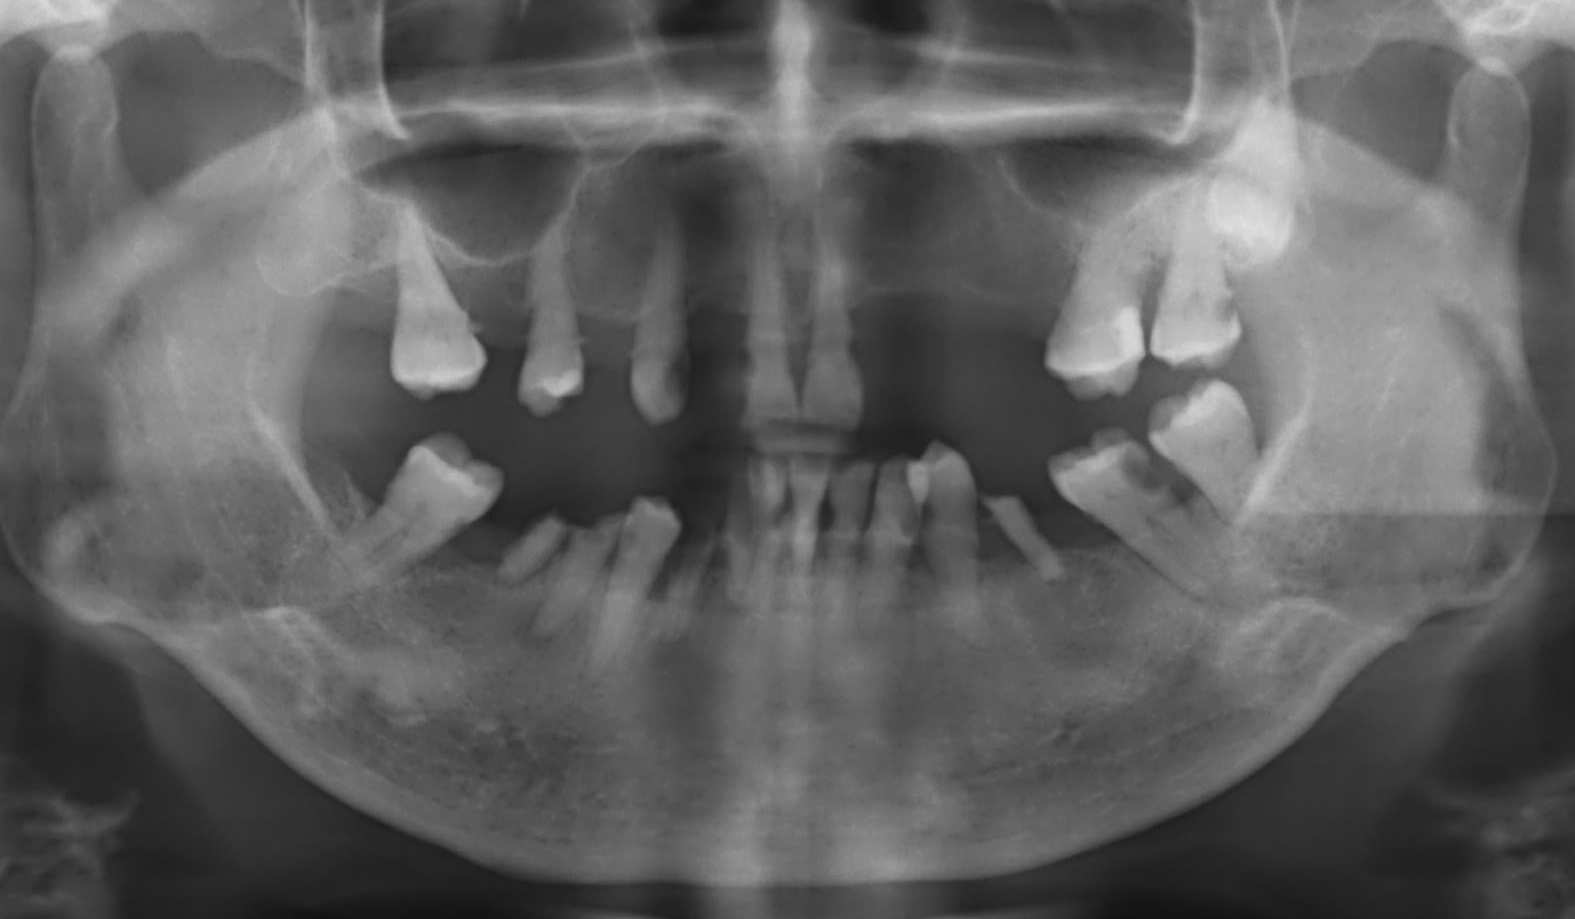

●第四章提到拔牙窩的改變,這也是這一版新增的章節。這邊簡單整理拔牙後,硬組織、軟組織的變化。篇幅不長,對年輕醫師,想簡單看一篇統整文章,可以從這裡開始。